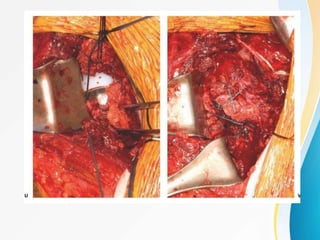

SURGICAL TECHNIQUES FOR ORIF OF

AN UNSTABLE DISPLACED 3 PART PHF

• for succesful reduction – 3 part converted to 2 part at the humeral

head i.e humeral articular part with the attached lt and gt

into 1 part with the shaft

4 steps

• surgical approach and axillary nerve identification

• long head of biceps tendon,rotator cuff suture and humeral head

assesment

• reduction with temporary k wire fixation and fluoroscopc assesment

• final fixation and suturing of rotator cuff to plate.

STEP 2

• Long head of biceps tendon is identified at the

bicipital groove .

• no 2 ethibond placed at Lt and GT to mobilise the

# fragments which assist with the reduction

• suture at Lt pulled laterally to correct retroversion

of the humeral head

• suture at Gt pulled into downward direction to

correct varus deformity

• subscapularis tendon attached to Lt should be

carefully protected to avoid avn of articular part.

STEP 3

• the plate is placed 5mm lateral to the bicipital

groove

• 5-8mm below the tip of GT.

• k wire is used for temporary fixation of the

reduced 2 part # of the head with the aid of suture

traction

• a simple compression screw is placed at the oval

hole of the plate.

• plate is used to assist in reduction of the head and

shaft part

STEP 4

• once the reduction is confirmed remaining

screws are placed at the head and shaft.

• calcar screws are placed supporting the reduced

calcar area.

• sutures attached to the rotator cuff are secured

to the plate holes.